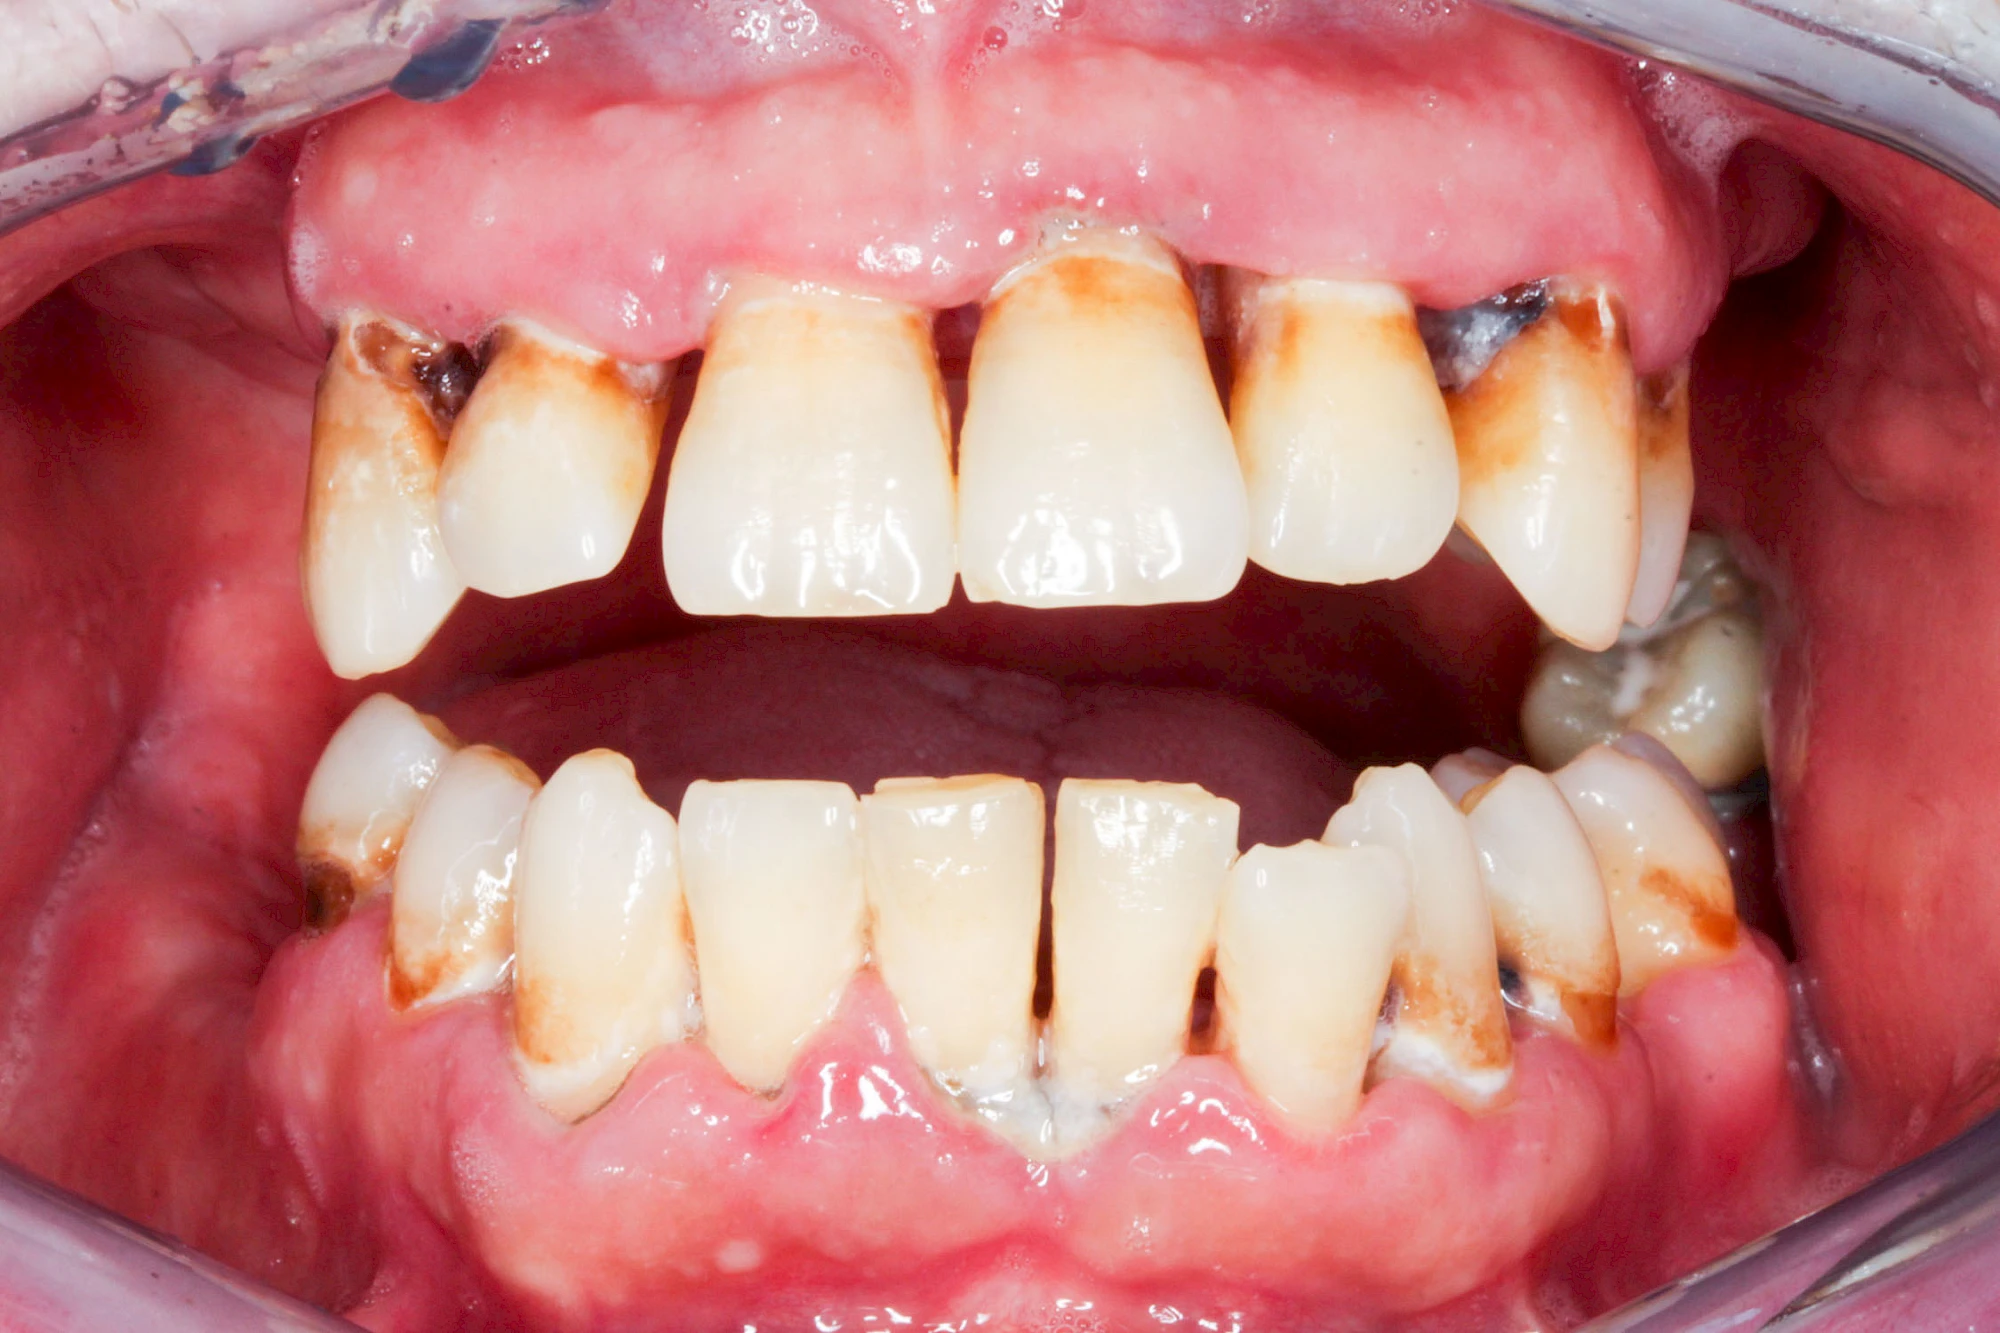

Ist zunächst nur das Zahnfleisch von der Entzündung betroffen, spricht man von Gingivitis. Später, wenn auch der Knochen um die Zähne herum entzündet ist, spricht man von einer Parodontitis. Bei der Parodontitis wird der Knochen nach und nach abgebaut und das Zahnfleisch zieht sich zurück. Die Zahnhälse und Zahnwurzeloberflächen liegen mehr und mehr frei. Die Zähne werden zunehmend lockerer und fallen schließlich aus.